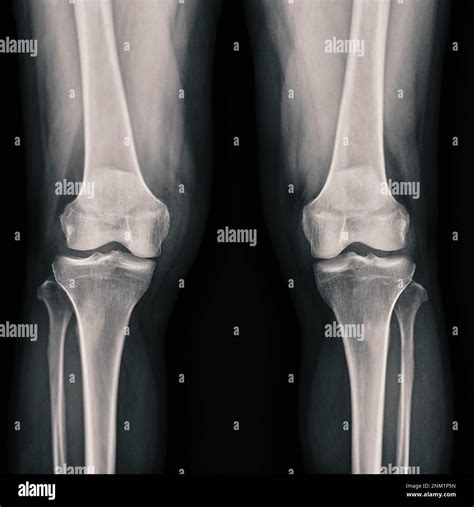

Healthy Knee Xrays

Interpreting Healthy Knee X-rays

Interpreting knee X-rays requires a trained eye. Here are some key features that radiologists look for in Healthy Knee X-rays:

• Bone Structure: The bones of the knee, including the femur, tibia, and patella, should appear smooth and intact without any fractures or deformities.

• Joint Space: The space between the bones should be uniform and not narrowed, which can indicate wear and tear or arthritis.

• Soft Tissue: While X-rays primarily show bone, the soft tissue around the knee should appear normal without any signs of swelling or inflammation.

• Alignment: The knee joint should be properly aligned, with no signs of dislocation or misalignment.